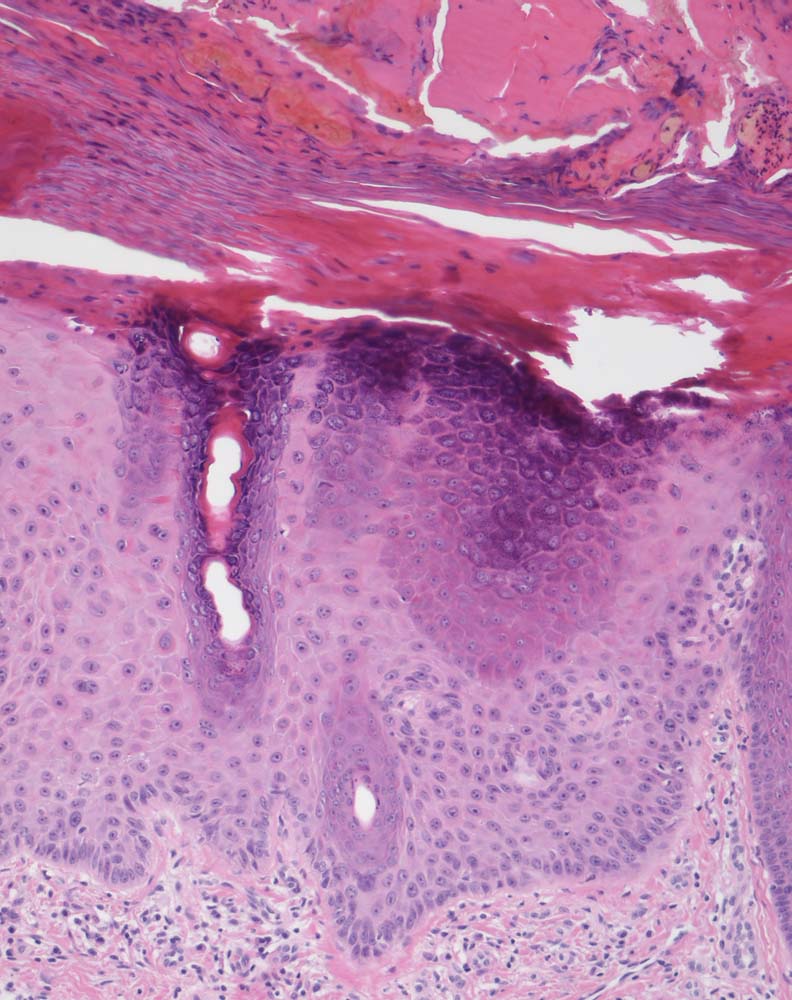

Die Epidermis zeigt obligat dysplastische Veränderungen. Die Dysplasie kann sich auf das untereste Epitheldrittel beschränken (leichte Dysplasie) oder die gesamte Epithelbreite betreffen (=bowenoide aktinische Keratose bzw. Carcinoma in situ). In der Dermis findet sich als Zeichen der chronischen UV Schädigung der Haut immer eine ausgeprägte solare Elastose. Das histologische Bild ist abgesehen von diesen zwei obligaten Befunden sehr variabel. Dyskeratotische Zellen und Mitosen finden sich häufig. Charakteristisch ist auch das Vorliegen einer alternierenden Para- und Orthokeratose, die unterschiedlich stark ausgeprägt ist. Manchmal findet man eine Atrophie der Epidermis mit schmalem Stratum corneum oder umgekehrt eine massive Hyperkeratose wie beim Cornu cutaneum. Akrosyringium und innere Abschnitte der Haarfollikel sind von den dysplastischen Veränderungen ausgespart. Die Epidermis zeigt häufig eine unregelmäßige Hyperplasie mit in das Stratum papillare reichenden Knospen. Bei Ausdehnung der Dysplasie entlang von Haarfollikeln in die Tiefe, können sich bei zu oberflächlicher Abtragung der Läsion Lokalredzidive ausbilden.

• Hyperparakeratotische Verhornung mit erkennbaren Kernresten in der Hornschicht.

• Epitheldysplasie: Reifungs- und Schichtungsstörung der Epidermis mit fokalem Polaritätsverlust der Keratinozyten, Atypien der Keratinozyten (hyperchromatische, pleomorphe und entrundete Zellkerne mit irregulärer Kernmembran und prominenten Nukleolen, vergrösserte Zellkerne mit hoher Kern-Plasmarelation) bis in obere Schichten der Epidermis. Dyskeratosen (hypereosinophile abgerundete Keratinozyten mit pyknotischem Zellkern als Zeichen der Verhornungsstörung). Crowding (überlappende Zellkerne).

• Zahlreiche, teils atypische (=multipolare) Mitosefiguren in allen Epidermislagen.

• Adnexstrukturen (Infundibulum und Akrosyringium) sind nur oberflächlich betroffen von den dysplastischen Veränderungen.